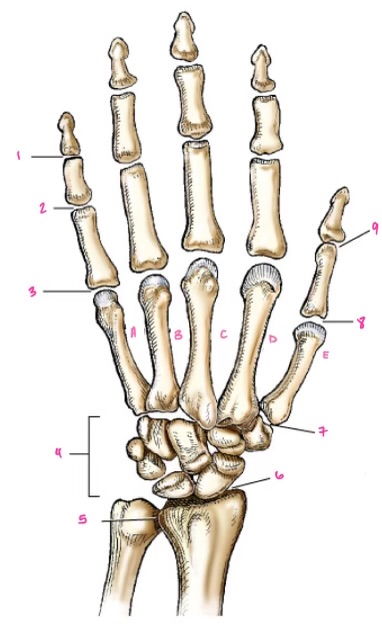

1

1

Hamate

2

2

Capitate

3

3

pisiform

4

9

Trapezoid

5

10

Trapezium

6

11

Scaphoid

7

14

Lunate

8

15

Triquetrum

9

16

Pisiform

10

17

Capitate

11

18

Hamate

1

Distal interphalangeal

13

2

Proximal Interphalangeal

14

3

Metacarpophalangeal

15

4

Intercapals

16

5

Distal radioulnar

17

6

Radiocarpal

18

7

Carpometacarpals

19

8

Metacarpophalangeal

20

9

Interphalangeal

7

Trapezoid

22

8

Trapzium

23

9

Capitate

24

10

Scaphoid

25

11

Lunate

26

13

Carpus

27

14

Triquetrul

28

15

Hamate

29

16

Metacarpus

30

17

Phalanxes